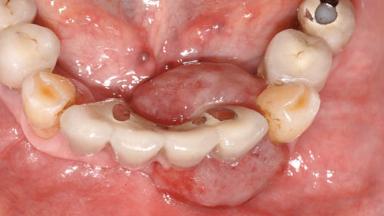

# of Teeth 10

# of Implants 5

Type of Implants One-Piece

Prosthesis Type FDP